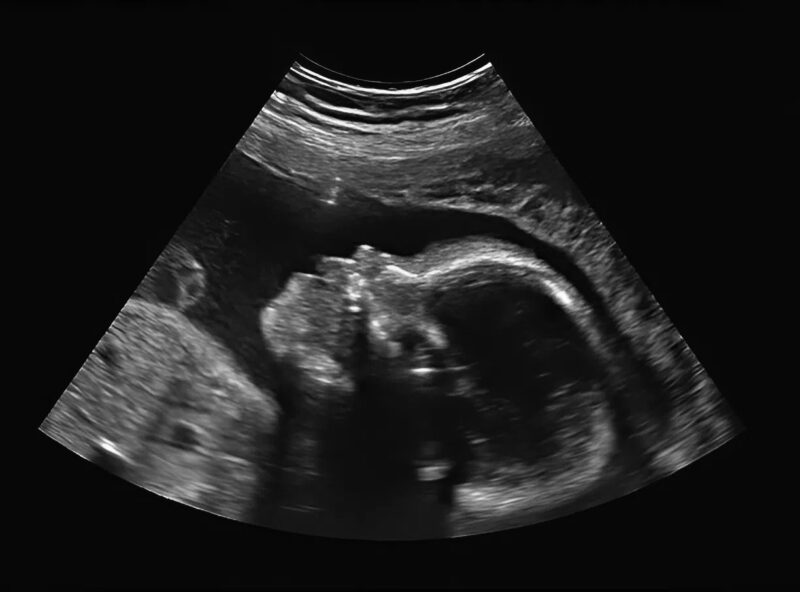

The screen flickered to life, showing the familiar shapes and movements of my little one 👣. I smiled faintly, hoping to see a healthy, kicking baby. But then the doctor’s expression changed. His brow furrowed, and he was silent for a long moment. My smile faltered 😳.

I sat there, staring at the screen. My baby was moving, waving tiny arms, and I could see the little heart beating rapidly ❤️. Even though something was missing, the life inside me was perfect in its own way. My mind began to race with questions: “How will I raise this baby? Will they face challenges? Will I be able to protect them?”